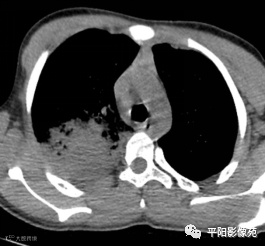

10天后再次复查CT:较前有所好转

影像特征:X线片右肺中上野片状高密度影,下缘以叶间裂为界,上缘及外侧缘模糊;CT位于右肺上叶后段,呈片状实变影,内见支气管影,边缘模糊。

影像诊断:右肺上叶大叶性肺炎。